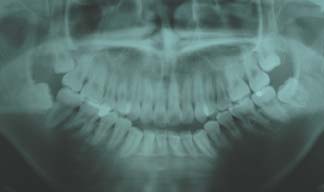

1.叢生(乱ぐい歯) 歯が重なり合ってでこぼこしています

治療前

上顎両側4番を抜歯

下顎両側4番も抜歯